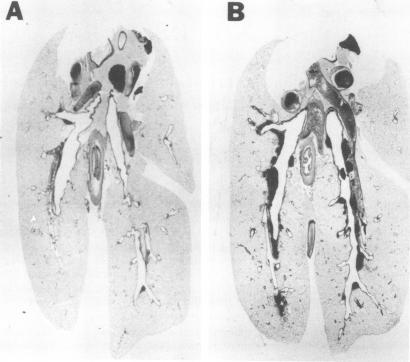

肺炎支原体感染大鼠肺部淋巴细胞的免疫荧光特征分析

Immunofluorescent characterization of lymphocytes in lungs of rats infected with Mycoplasma pulmonis.

Immunofluorescence was used to determine the relative percentages of T and B lymphocytes found in the lungs of normal and Mycoplasma pulmonis-infected F344 rats. Lymphocytes recovered from controls were approximately 25% T, 25% B, and 50% unclassified mononuclear cells. Infected animals had a 2.6-fold greater number of T cells and IgA-bearing cells, and a 1.6-fold greater number of unclassified mononuclear cells. These studies show that M. pulmonis infection significantly alters lung lymphocyte populations both quantitatively and in subpopulation distribution. Therefore, future studies of rat lung lymphocytes should utilize animals known to be free of this ubiquitous respiratory pathogen.

采用免疫荧光法测定正常和感染肺炎支原体的F344大鼠肺组织中T淋巴细胞和B淋巴细胞的相对百分比。从对照组回收的淋巴细胞中,T细胞约占25%,B细胞约占25%,未分类的单核细胞约占50%。感染动物的T细胞和含IgA细胞数量增加了2.6倍,未分类的单核细胞数量增加了1.6倍。这些研究表明,肺炎支原体感染显著改变了肺淋巴细胞群体的数量和亚群分布。因此,未来对大鼠肺淋巴细胞的研究应使用已知无这种常见呼吸道病原体的动物。